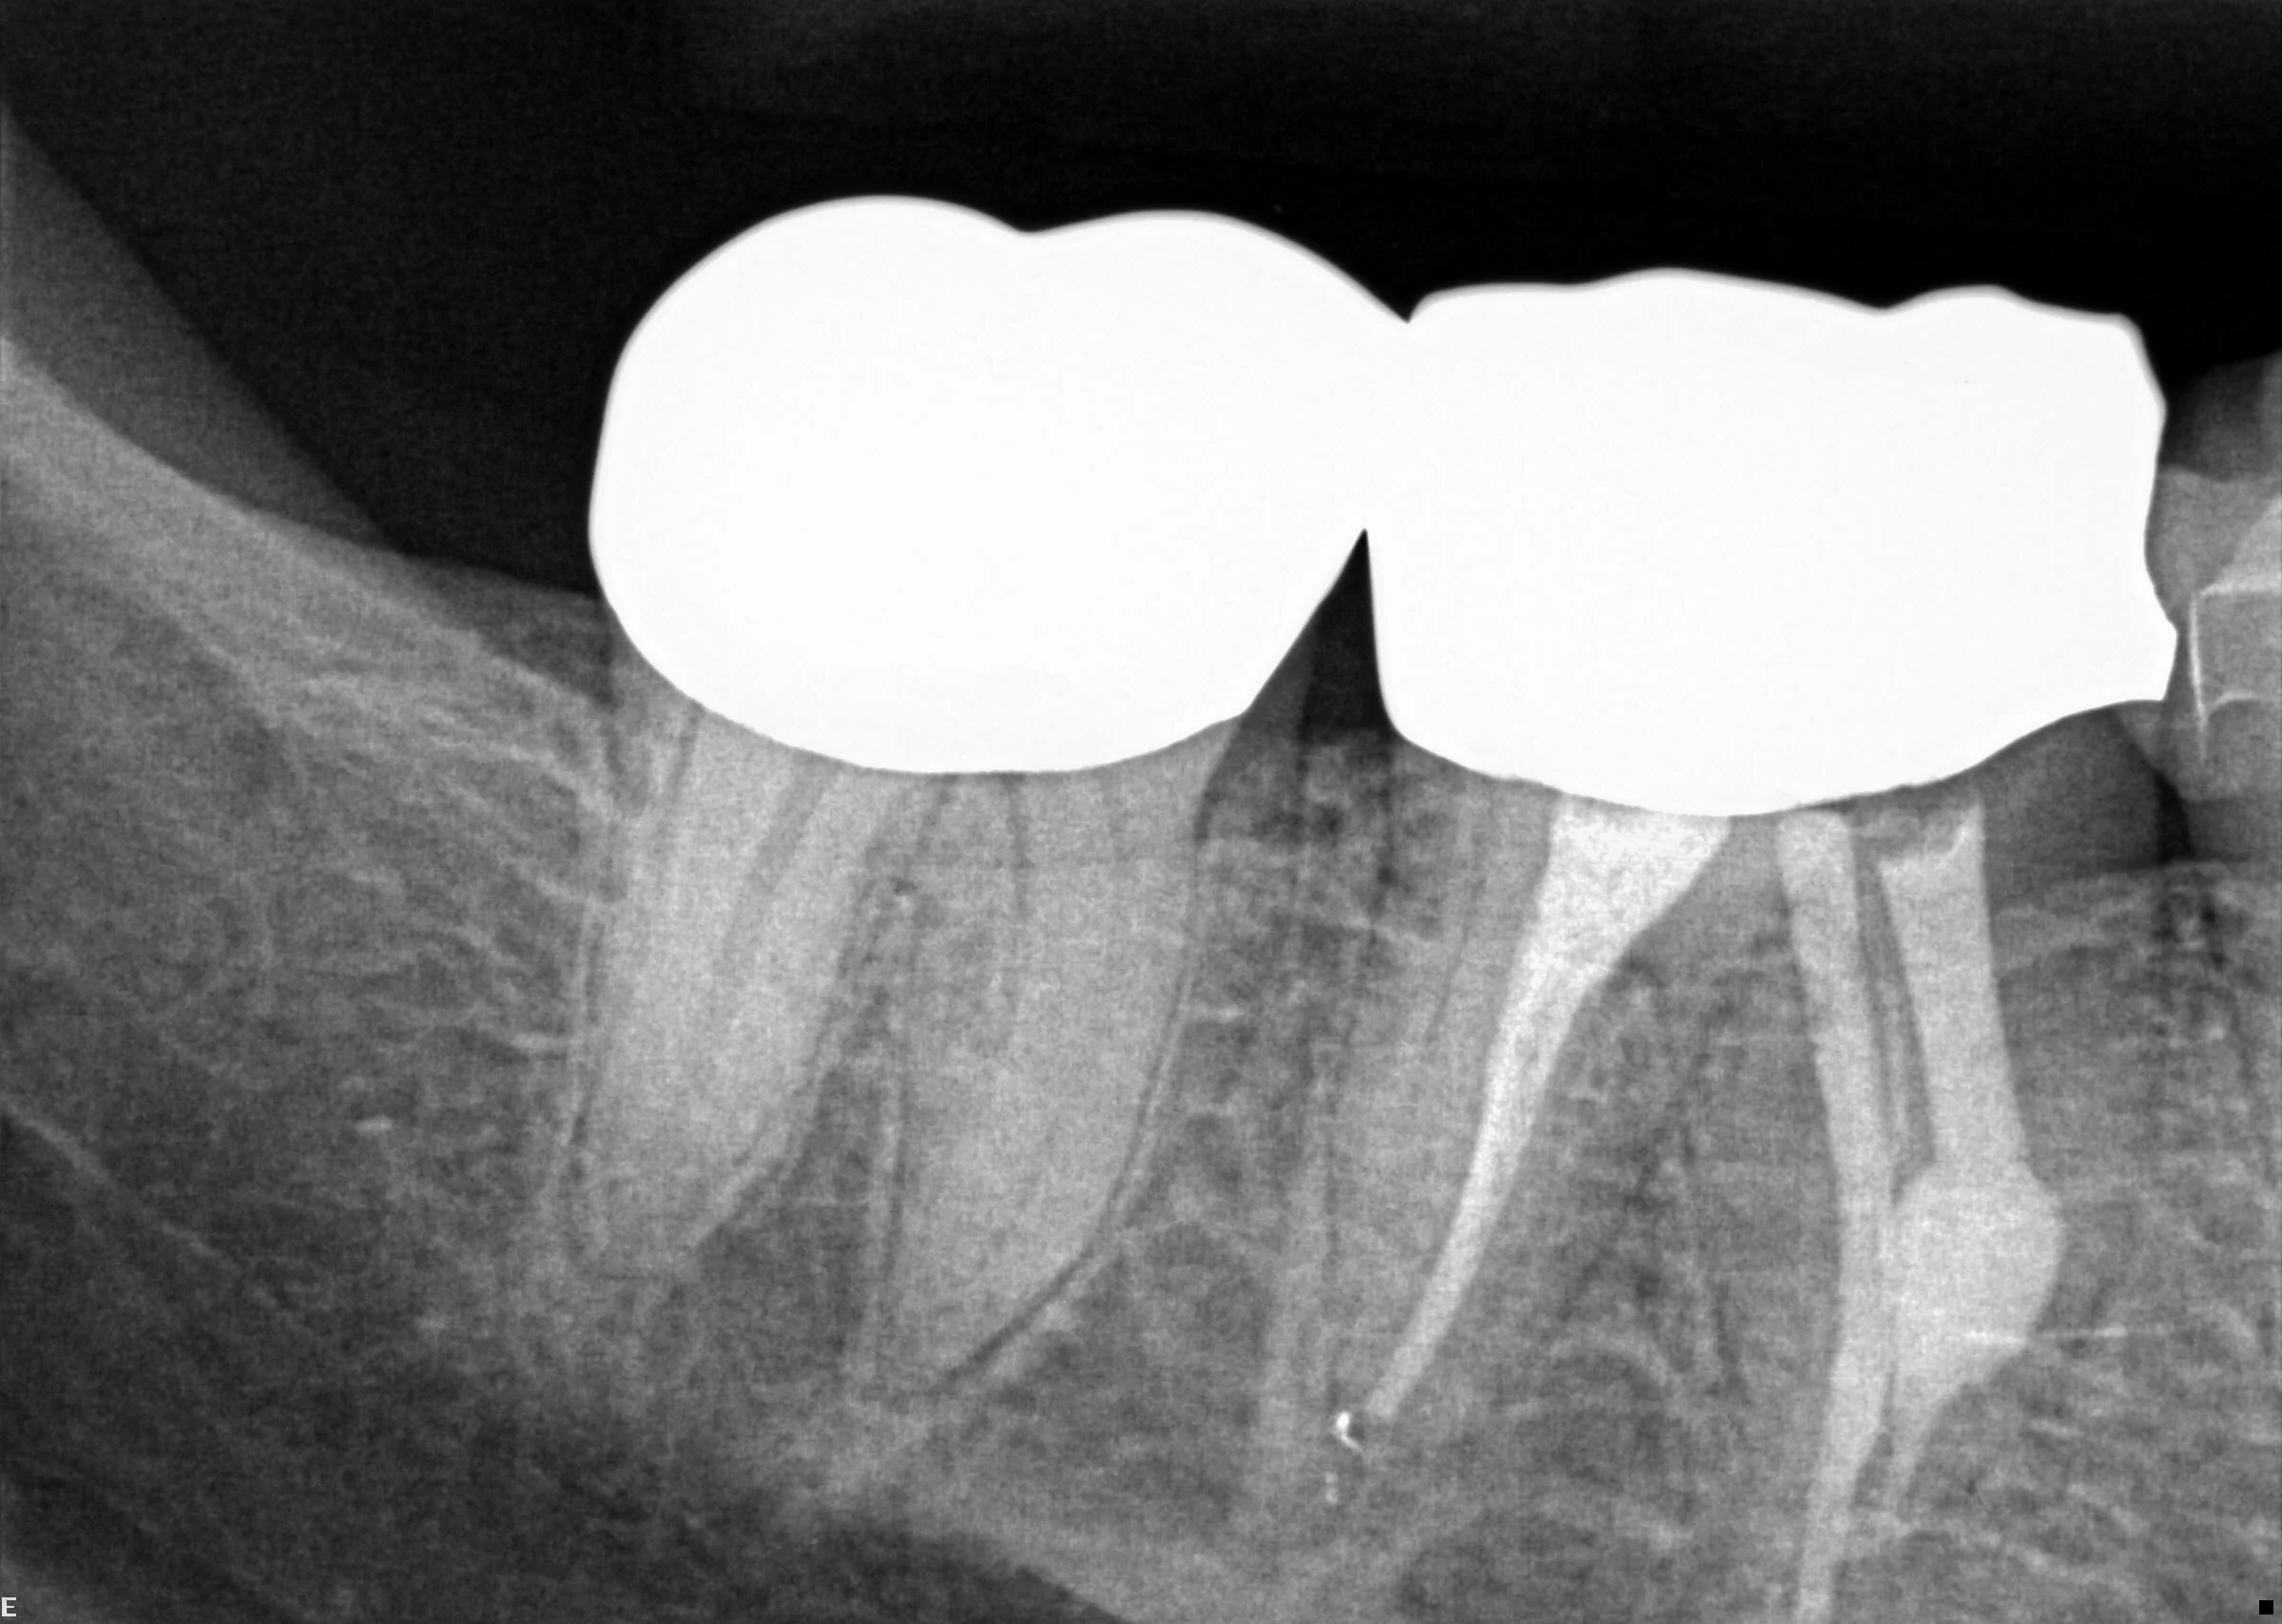

The following example demonstrates how CBCT imagery can assist in diagnosing resorption. In this particular case, internal resorption occurred in both the mesial and distal roots of tooth #30.

Cone Beam Computed Tomography (CBCT) creates 3-Dimensional images that provide detail standard dental radiographs cannot. This allows an endodontist to view teeth from multiple angles, which can reveal anatomical variations or pathology a regular 2-D image fails to disclose. The information contained within CBCT can be invaluable while diagnosing and treating simple and complex cases.

Our CBCT unit utilizes Planmeca Ultra Low Dose™ – a proprietary low dose 3D imaging protocol that enables CBCT imaging with an even lower patient radiation dose than standard panoramic imaging.

This allows capturing an image with a decreased effective patient dose without any significant loss in image quality.